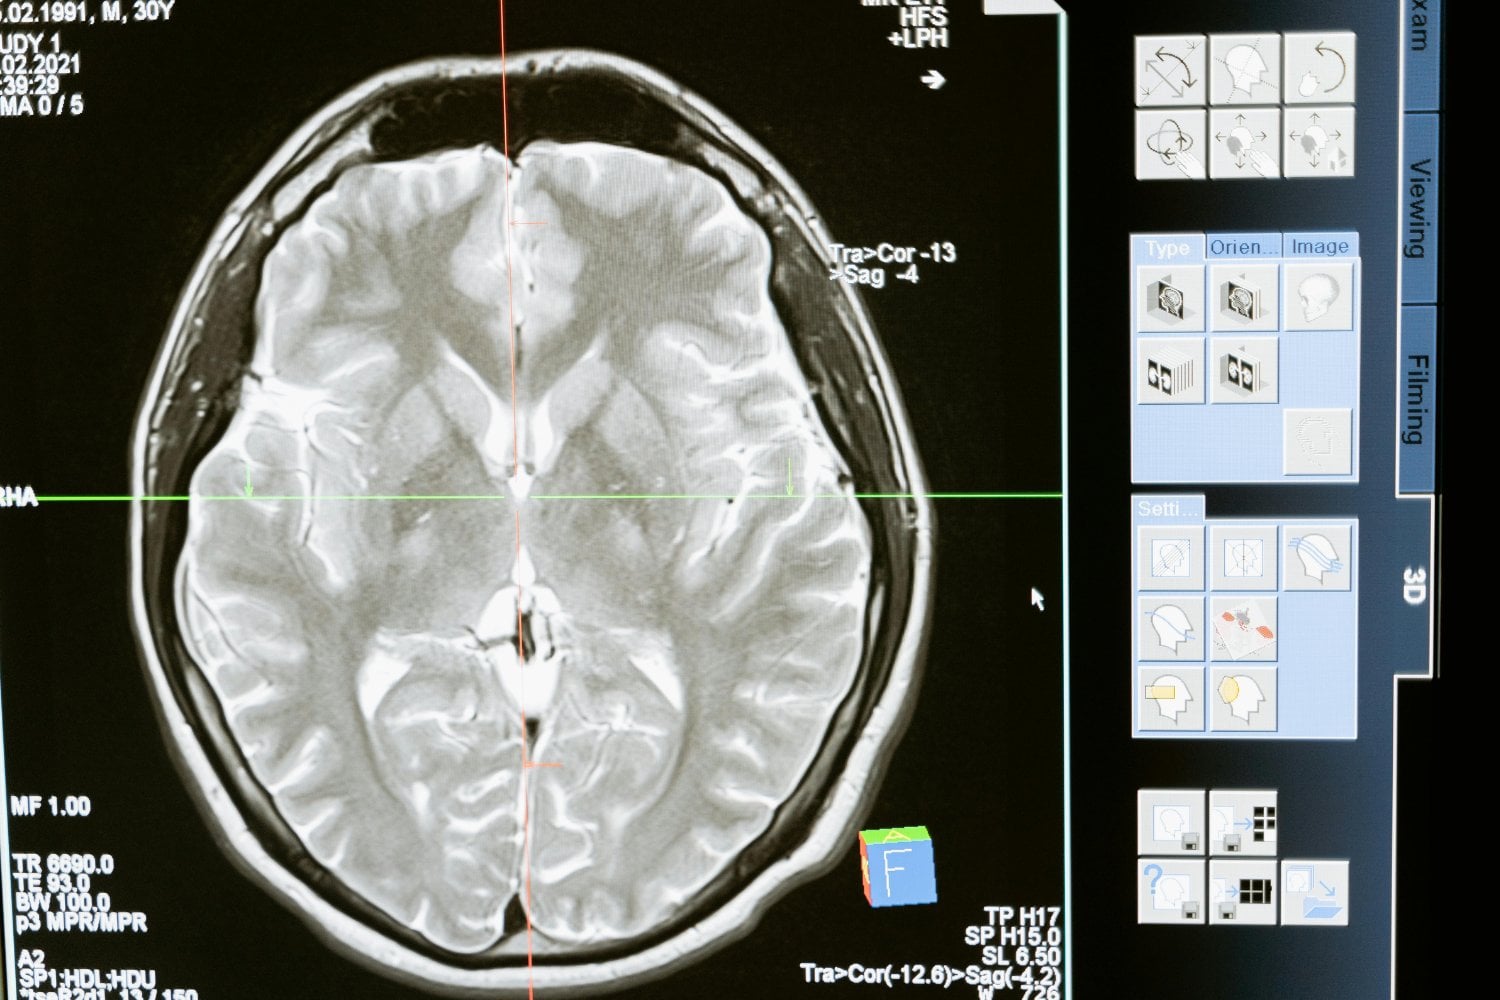

Uno de los aspectos más fascinantes del cerebro es su plasticidad neuronal, es decir, la capacidad de sus neuronas para establecer nuevas conexiones. Este proceso es posible gracias a los axones, estructuras celulares que transmiten señales a través de neurotransmisores. Estas sustancias químicas permiten la comunicación entre neuronas mediante sinapsis, pequeños espacios en los que la información pasa de una célula a otra.

A diferencia de un ordenador, donde la información se almacena de manera estructurada en un disco duro, el cerebro funciona mediante redes neuronales interconectadas. Un recuerdo no reside en una sola neurona, sino en una compleja red de conexiones que se reorganizan constantemente según nuestras experiencias y necesidades.